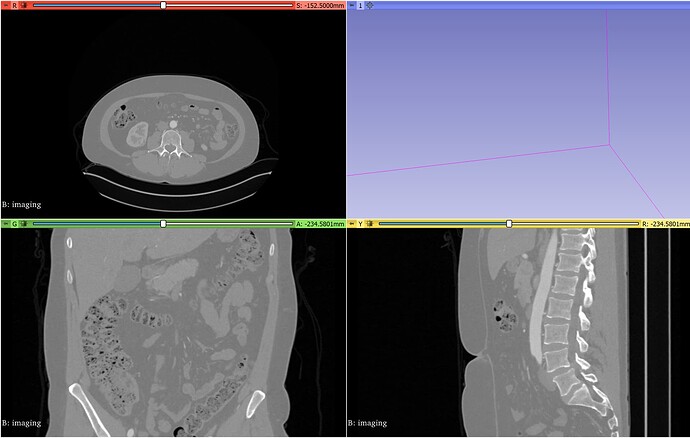

When I first import my imaging file, it looks like this: